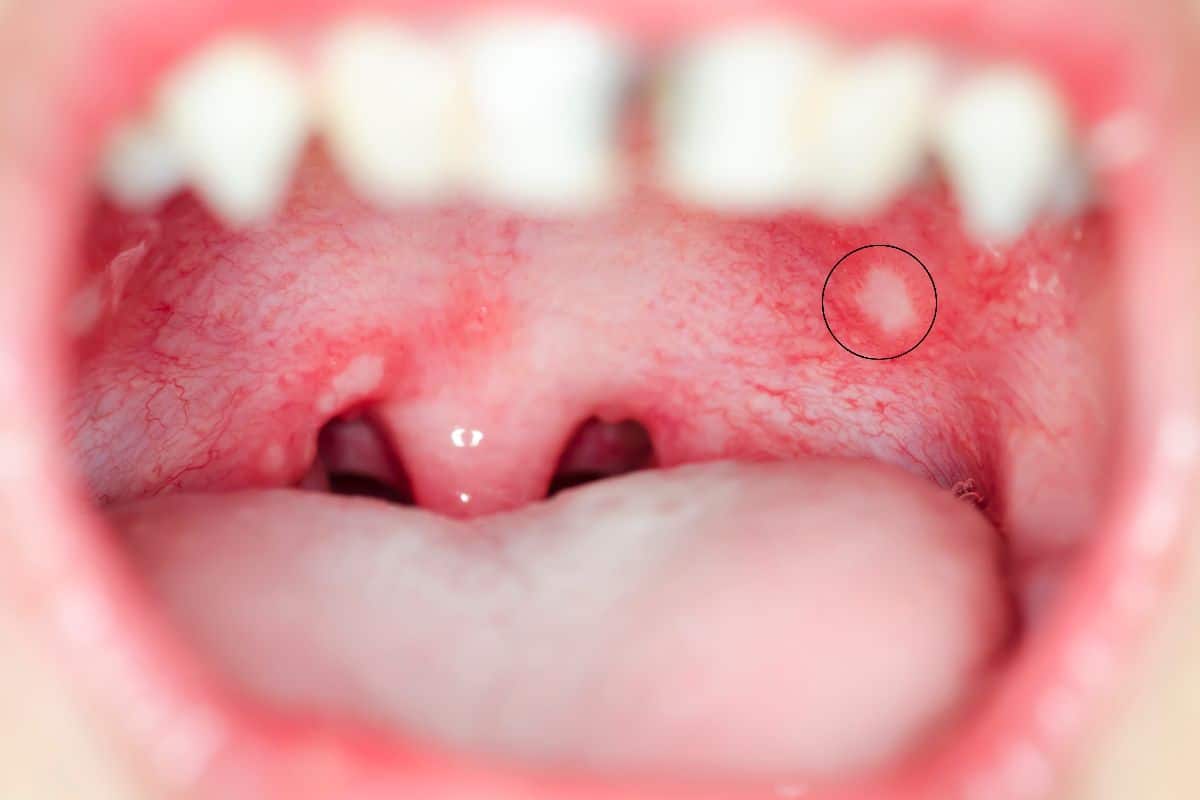

Canker sores are small, painful lesions that can appear on the hard or soft palate.

They appear as round or oval sores with a white or yellow center and a red border. Unlike cold sores, canker sores are not contagious and are not caused by a virus. They are typically triggered by stress, minor mouth injuries, hormonal changes, food sensitivities, or nutritional deficiencies — particularly low levels of iron, folate, or vitamin B12.

Most canker sores heal on their own within seven to fourteen days. Larger or persistent ones may need professional evaluation.